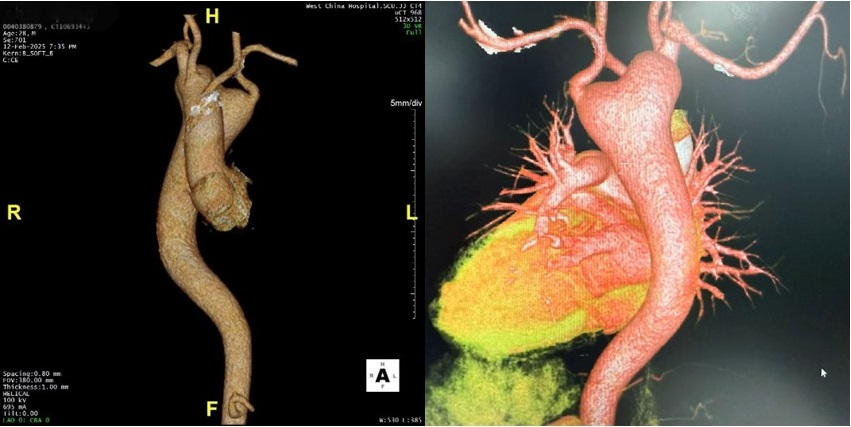

检查显示,病变不止于此。陈先生合并一系列血管畸形,包括右位主动脉弓、迷走左锁骨下动脉变异等。所谓右位主动脉弓,就是本该向左侧弯曲的主动脉弓,在胸腔内拐向右侧。

更棘手的是,其主动脉弓降部有一个巨大的Kommerell憩室,为先天性发育畸形所致,破裂率为6%。若进一步发展至主动脉夹层,破裂率将高达44%。

最终,经过多学科专家团队的反复论证,陈先生的手术方案确认:进行一期外科矫治,完成Bentall(主动脉根部置换术)手术、巨大Kommerell憩室切除、右位主动脉弓后半弓及降主动脉置换、迷走左锁骨下动脉重建手术。

术后第7天,陈先生转回普通病房,无相关并发症,当天能下床进行少量活动。术后复查胸部血管CT提示,主动脉根部瘤、Kommerell憩室完美切除;心脏彩超显示人工主动脉瓣功能良好。